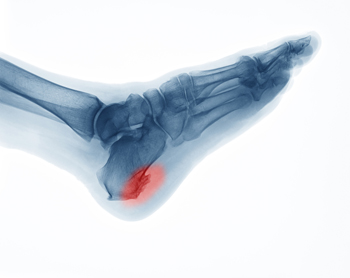

A heel spur takes the form of a bony-like growth. This is due to a calcium deposit that extends between the heel bone and foot arch. They can grow up to half an inch in length; however, they may not be outwardly visible. Because heel spurs tend to grow, increasing the overall discomfort felt, it’s important that you seek professional help as soon as pain is experienced for early detection.